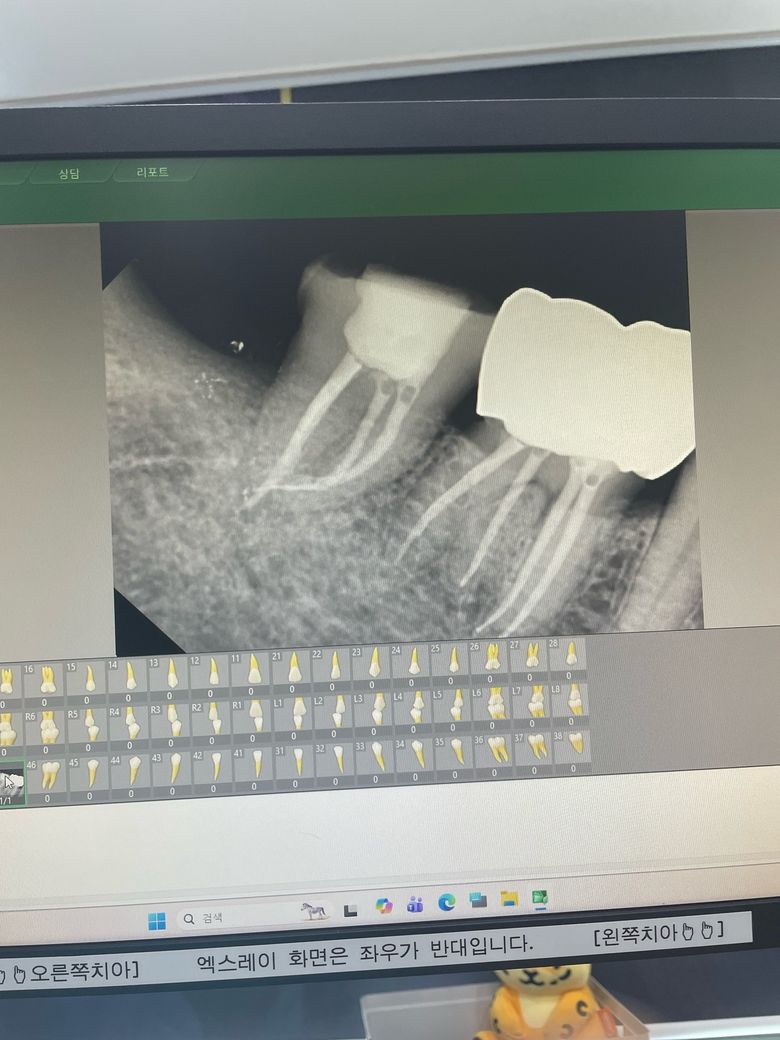

오버필링이라고 타 치과에서 진단받았습니다

사랑니옆옆치아 신경치료 12월17일

사랑니옆치아신경치료 12월23일

열감이있고 씹을땐 일주일에 한번 양치할때 아프고 통증없고 거슬리게해요

본치과에서는 사랑니뺀자리 문제라하고

타치과에서는 오버필링이라고 합니다

두달이지나도 사랑니문제가 되나요

오버필링 치료가 어렵다고 하는데

발치해야하나요 ㅜㅜ

일단 씹을때 아픈 증상은 없으니 좀 더 기다려볼만 합니다. 열감이 있는게 불편해서 당장 발치를 해야 할 정도는 아닐 것 같습니다.

오버필링 때문에 신경치료 결과가 영향을 받는 경우는 많지 않습니다.